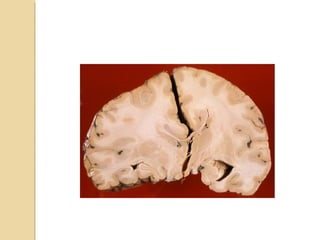

CONTUSION/LACERATIONSCONTUSION/LACERATIONS Most common sourceof traumatic SAH Contusion: must involve the superficial gray matter Laceration: contusion + tear of pia-arachnoid Affects the crests of gyri Hemorrhage present ½ cases and occur at right angles to the cortical surface Located near the irregular bony contours: poles of frontal lobes, temporal lobes, inferior cerebellar hemispheres

• 24.